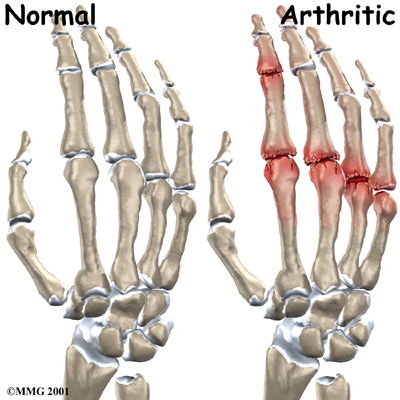

The bones in the palm of the hand are called metacarpals. One metacarpal connects to each finger and thumb. Small bone shafts called phalanges line up to form each finger and thumb.

The bones in the palm of the hand are called metacarpals. One metacarpal connects to each finger and thumb. Small bone shafts called phalanges line up to form each finger and thumb.

The main knuckle joint is formed by the connection of the phalanges to the metacarpals. This joint is called the metacarpophalangeal joint (MCP joint). The MCP joint acts like a hinge when you bend and straighten your fingers and thumb.

The in each finger are separated by two joints, called interphalangeal joints (IP joints). The one closest to the MCP joint (knuckle) is called the proximal IP joint (PIP joint). The joint near the end of the finger is called the distal IP joint (DIP joint). The thumb only has one IP joint between the two thumb bones. The IP joints of the digits also work like hinge joints when you bend and straighten your hand.

The finger and thumb joints are covered on the ends with . This white, shiny material has a rubbery consistency. The function of articular cartilage is to absorb shock and provide an extremely smooth surface to facilitate motion. There is articular cartilage essentially everywhere that two bony surfaces move against one another, or articulate.